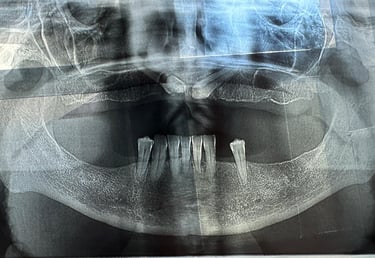

Se deceleaza imagistic o formatiune tumorala radiotransparenta, de mari dimensiuni, localizata la nivelul intregului grup frontal mandibular.

Dupa examenul clinic si imagistic se pune diagnosticul prezumtiv de formatiune tumorala chistica (chist radicular de mari dimensiuni). Se intervine chirurgical realizandu-se extractiile dintilor cauzali, irecuperabili, rezectii apicale a dintilor implicati chistic, care au fost tratati endodontic in prealabil. Piesa operatorie a fost trimisa catre examenul histopatologic, diagnosticul fiind chist radicular fara atipii.